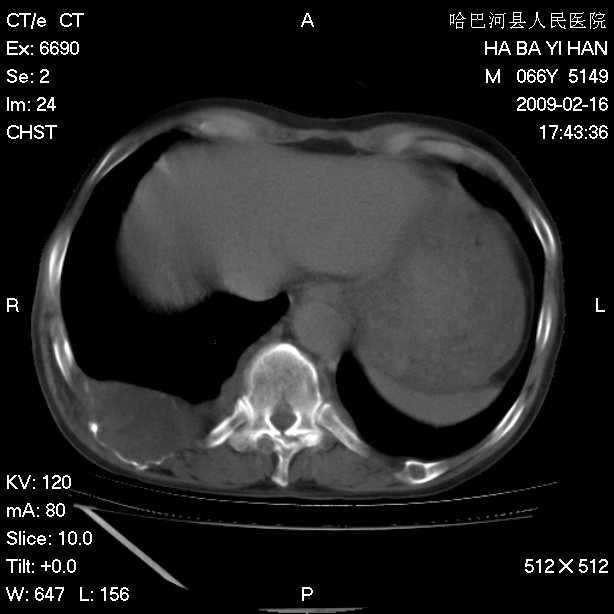

以下是引用huangxun4321在2009-2-16 20:18:00的发言:[br]部分病灶可见硬化边,部分可见骨质破坏消失,部分病灶内可见骨脊,说明病灶内既有良性病变,又有恶性病变,考虑骨巨细胞瘤恶变,未除骨纤恶变,畸形性骨炎少见,亦要考虑.

以下是引用731208在2009-2-16 20:31:00的发言:[br]考虑恶性胸膜间皮瘤并肋骨,脊柱转移。

以下是引用yijiansheng在2009-2-16 20:16:00的发言:[br]考虑恶性胸膜间皮瘤并肋骨,脊柱转移。

以下是引用形影不离在2009-2-16 19:55:00的发言:[br]考虑多发性转移瘤。